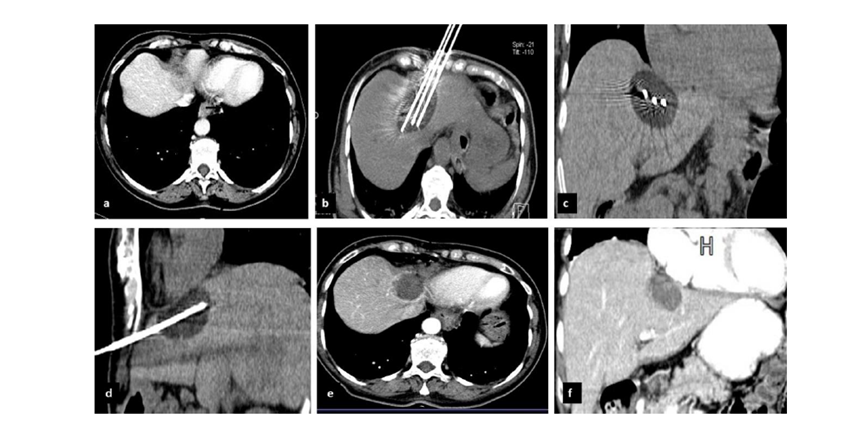

79 歲男性,肝轉(zhuǎn)移(結(jié)直腸癌)腫瘤的完全消融病例

( a ) 軸向 MRI 和 ( b ) 軸向 CT 顯示肝S8段有一個(gè)16mm的病灶,鄰近肝緣。( c )冷凍消融期間CT顯示放置了2個(gè)冷凍探針,低密度冰球包圍病灶。(d)術(shù)后1個(gè)月隨訪 CT顯示冰球?qū)?yīng)的壞死區(qū)域,未見復(fù)發(fā)。(e)術(shù)后6個(gè)月的CT,壞死區(qū)域縮小,未見復(fù)發(fā)。(f)與基線影像(g)相比,12個(gè)月后的FDG-PET/CT顯示未見FDG攝取。

62歲女性,肝轉(zhuǎn)移(卵巢癌)腫瘤的完全消融病例(a)軸向CT顯示病變位置毗鄰心臟和上腔靜脈(黑色箭頭)。(b)術(shù)中軸向CT掃描:使用三個(gè)冷凍探針。1個(gè)月后的軸向(e)和冠狀位(f)增強(qiáng)CT掃描顯示低密度區(qū)域,由于肉芽組織反應(yīng)引起的邊緣增強(qiáng)。